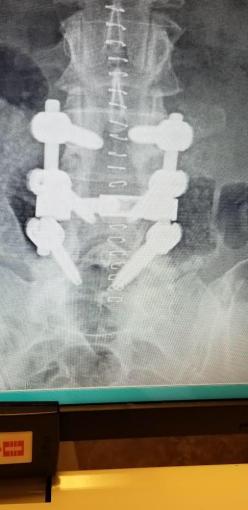

Before we hop into the pictures, I want to share with you that I will be having yet another doggone spine surgery on Wednesday of this week. As some longtime readers may remember, I had 2 such surgeries (in addition to a shoulder surgery!) in 2015 that kept me down and out for quite a long time, then 2 more in 2016. This one, too, will be very difficult (laminectomy, hardware replacement and fusion), but I’m hoping to have a clear enough head to bring you my 2017 Christmas decor along with…drumroll, please…a “Better Kansas City” segment taped right here in our home last Friday!!! I’ve been preparing for it since October (walking with the assistance of a cane and walker slows me down considerably!) and wanted it to be extra special knowing I will not be posting again for quite some time. I do hope you’ll look for that post (if the post-op pains and/or drugs aren’t too overwhelming!) coming sometime before Christmas. My husband will deliver a quick post on how I’m progressing along with a “proof of life” photo. 🙂 The surgery itself is expected to take only 3-4 hours (half the time of that 2nd one in 2015 that was 8 hours long!), and my hospital stay will be 3-4 days. Then it’s home to start getting better for 2018!!!